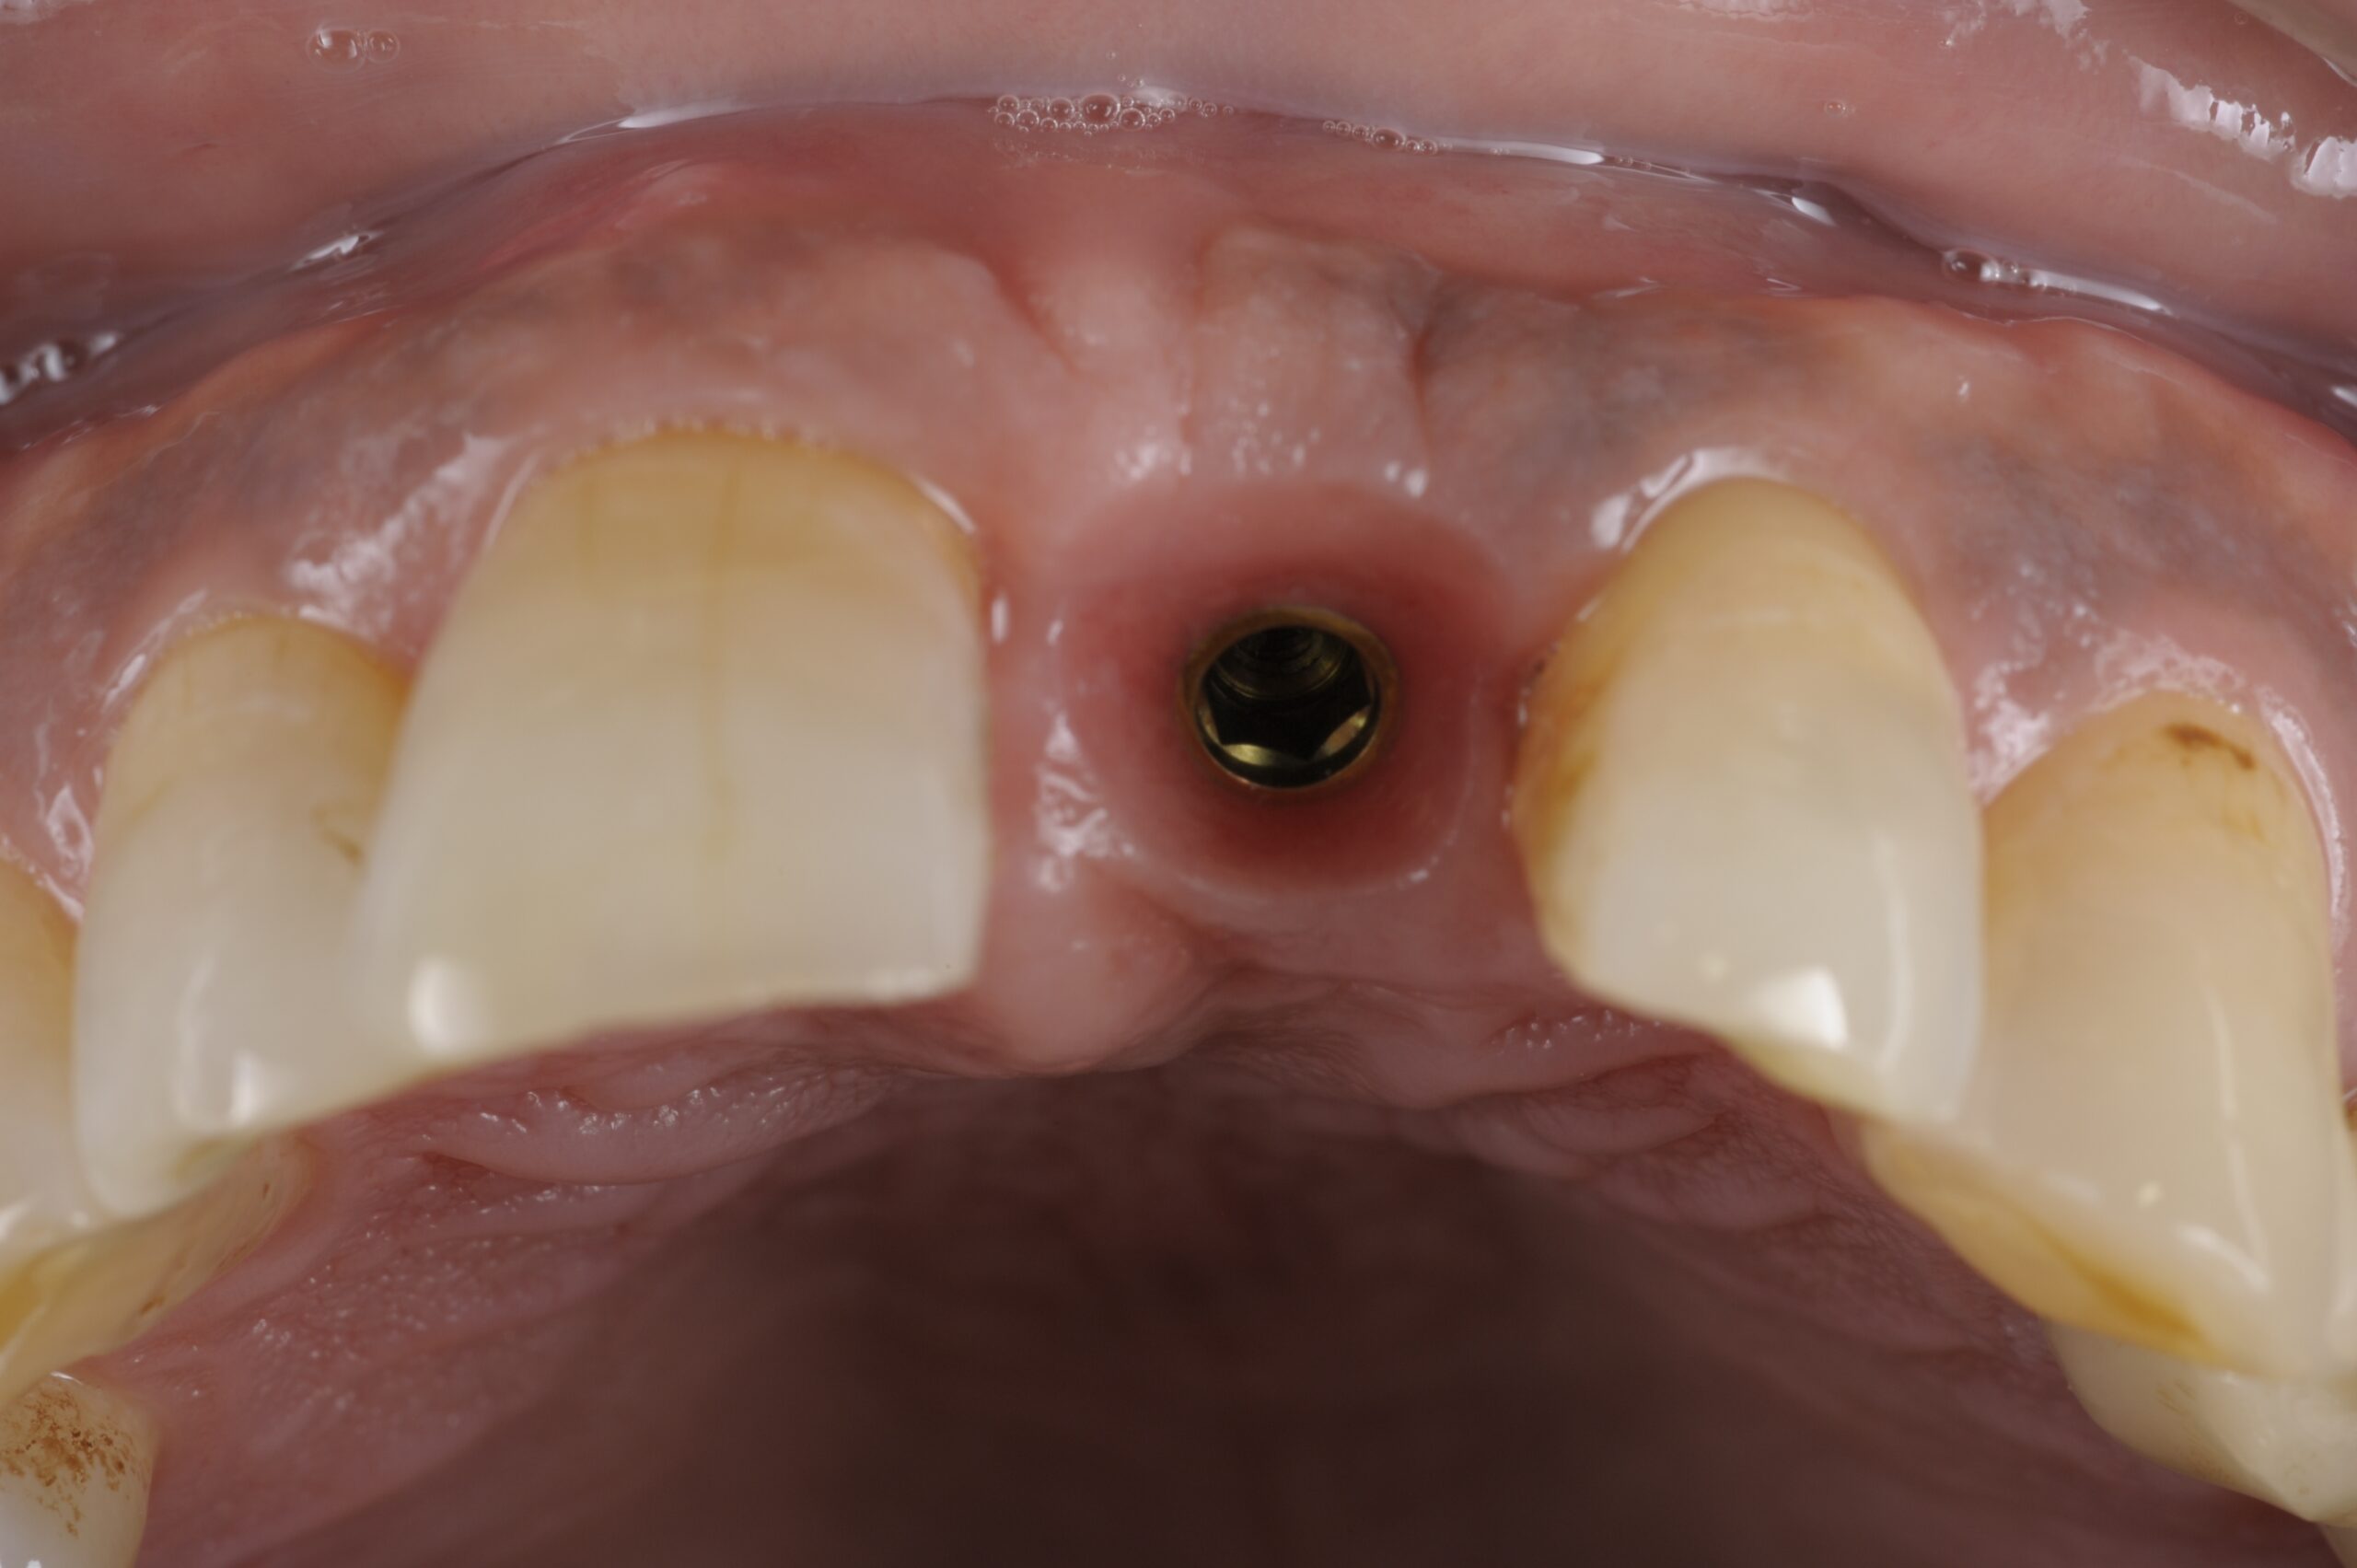

前歯インプラント症例

主訴 歯を入れたい(男性) 治療内容 1本インプラントの一般的な治療過程です。 プラマRFインプラントを埋入。

手術後3ヶ月待ち、骨とインプラントが固まったことを確認し、二次手術後に型取りを行っています。当院では、ほとんどの症例でデジタルでの型取りを行っています。

インプラントを埋入した部位に型取り用のパーツをはめ、3Dスキャナーにて型取りをし、ジルコニアクラウンの被せ物を作製しています。ご自身の歯と変わらないような仕上がりとなっています。

治療期間 約6ヶ月 費用 総額 ¥350,000-(税別) リスクと副作用 ・外科治療となるので、お身体の状態によっては受けれない場合がある(広範囲に適用可能な治療ですが、個々の患者様の状況によって適用外な場合もある)

・術後に多少の痛みや腫れが出ることがある